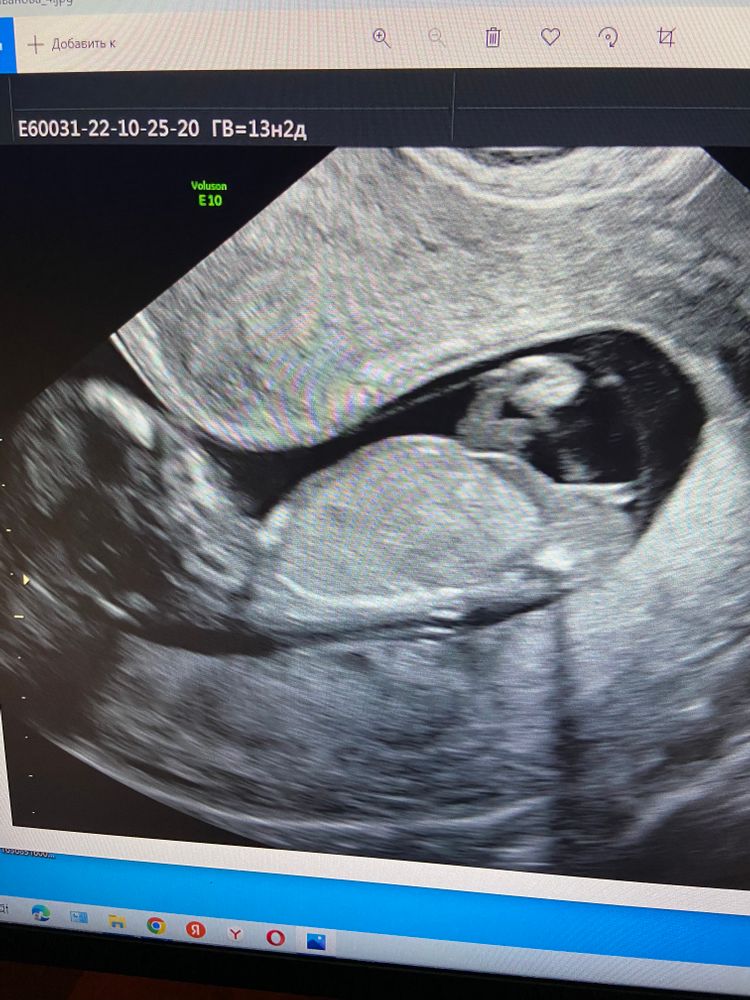

Первый скрининг

Хм, мне кажется девочка!🤔 странно…

Дочь)

Я бы сказала девочка, т.к. половой бугорок не высоко. Но узисту виднее, не я ж профессионал)

Девочка

Мне кажется доченька ❤️

И я девочку вижу по углу наклона бугорка

Мое мнение у вас девчушка 👧☀️🤷‍♀️

Половой бугорок параллельно позвоночнику.У меня такая же картина по узи-предположили девочку))Так что я тоже за девочку)